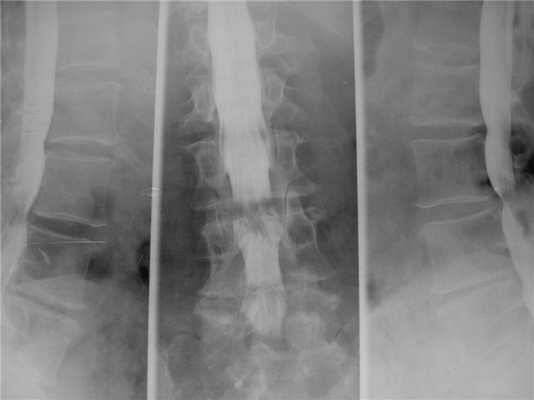

Нестабильность после декомпрессивной ламинэктомии. Рентгенография и МРТ позвоночника в сагиттальной и аксиальной плоскостях. Ламинэктомия на нескольких уровнях, постламинэктомический спондилолистез и дефект дуг.

Синдром смежного уровня. Стеноз позвоночного канала выше уровня стабилизации. Миелография.

Неустранённый стеноз позвоночного канала. Миелография.